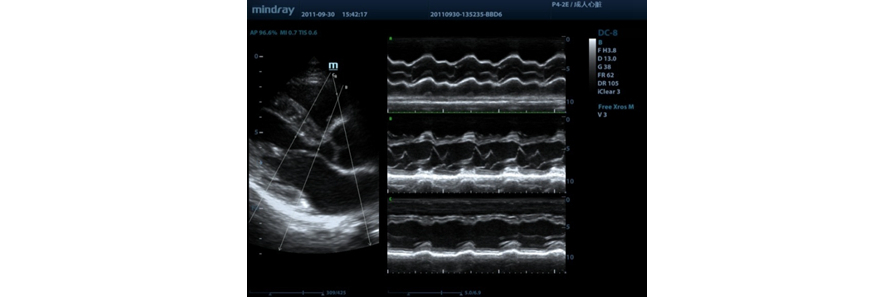

Free Xros M?

Observa??o anat?mica precisa com a coloca??o livre de linhas de amostra em qualquer ?ngulo. Melhores imagens por meio da exibi??o simult?nea de at├® 3 linhas de amostra.